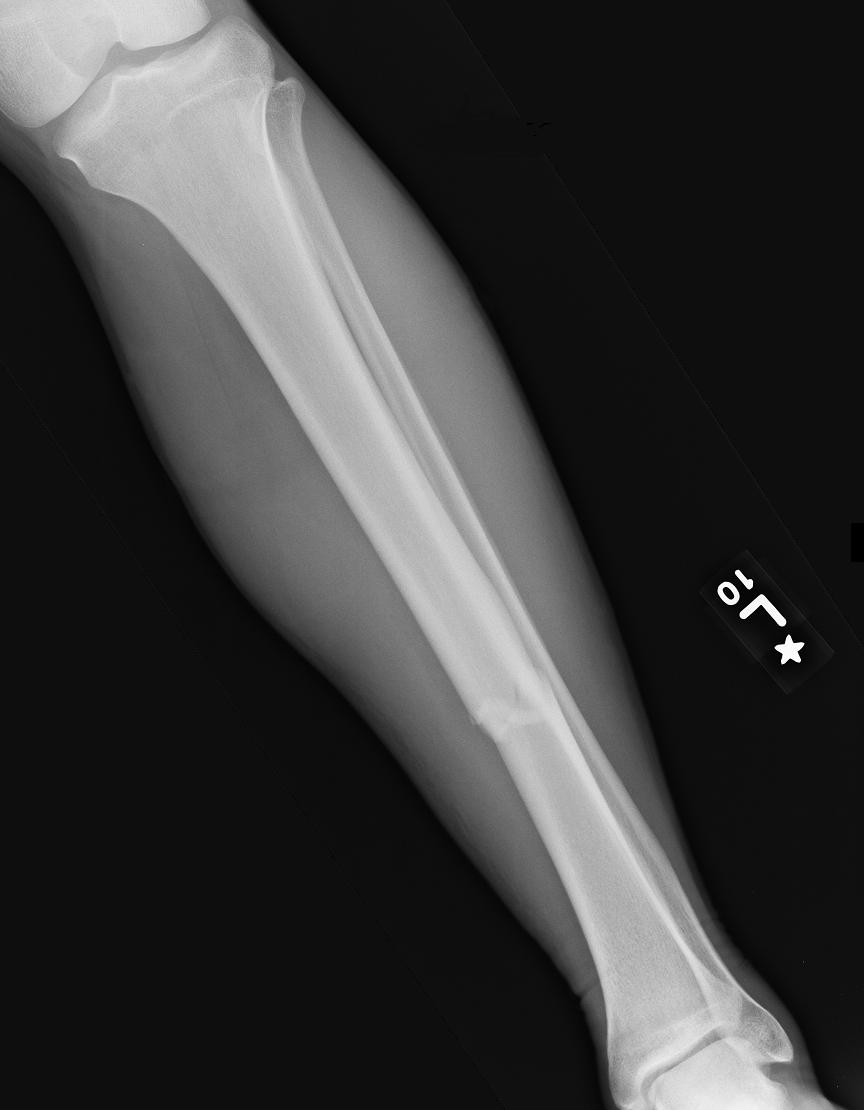

Fractures range from small partial cracks to complete breaks and can occur in any bone.

fracture In more severe cases, the bone may be broken into several fragments, known as a comminuted fracture. Overuse or repetitive motions can cause stress fractures. Fracture d�une porte, d�une serrure. Extends all the way across the bone (most common) transverse fracture: A fracture is a break in the continuity of a bone. An attorney intending on climbing the career ladder toward success finds an unlikely opponent in a manipulative criminal he. Rita riportò due fratture nell�incidente. Fractures usually fall within a set number of patterns.

orthopedics How to tell if my leg fracture is healing? Health Stack